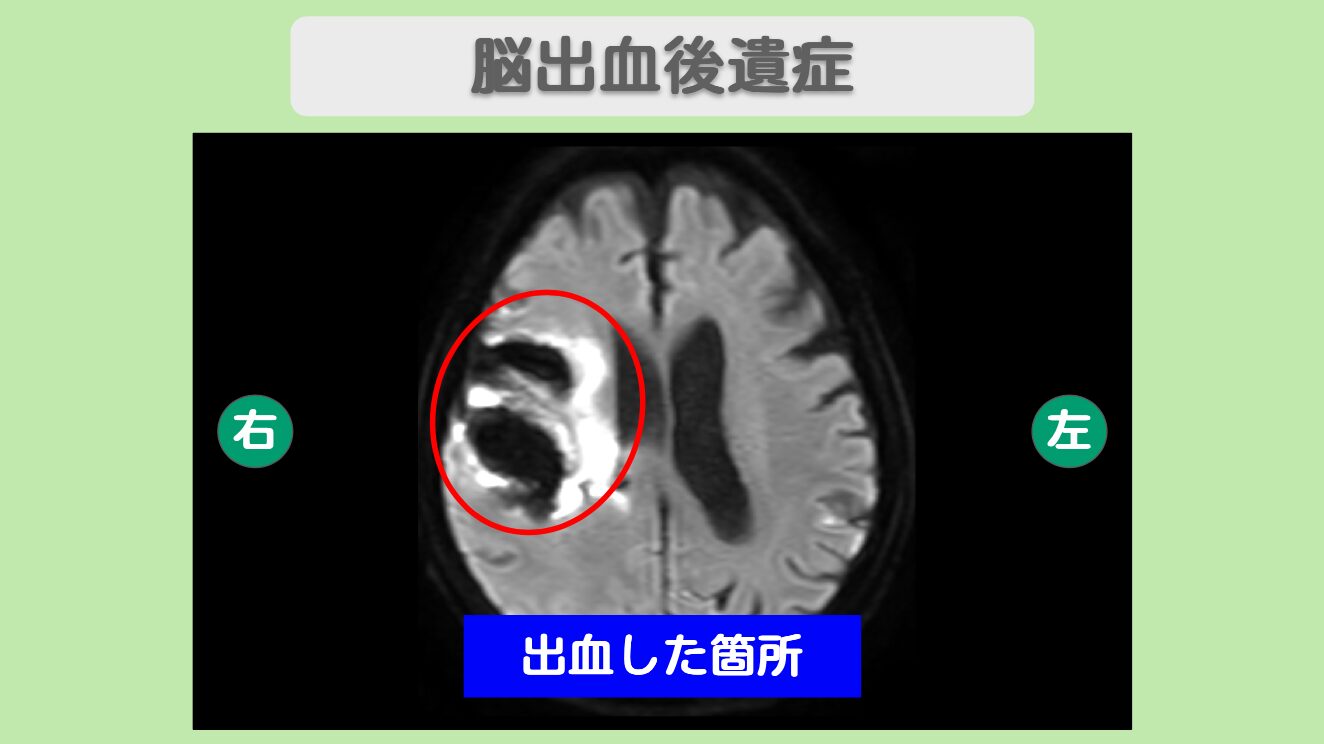

MRI所見

右皮質下出血と脳室内出血、さらにアルツハイマー型認知症により反応が低下し、ほとんどをベッド上で過ごされていた80代の患者様。幹細胞治療により発語が増え、表情が柔らかくなり、ご家族様との反応も改善されました。「今できる最善のことをしてあげたい」というご家族様の想いから始まった治療で、生活の質の向上という大きな成果が得られたのです。

患者様は、4-5年前から同じ物を何度も冷蔵庫にしまうなどの行動があり、2022年にアルツハイマー型認知症と診断されました。2024年10月に、突然の意識障害と嘔吐で救急搬送され、脳出血の診断を受けました。その2ヶ月後に新型コロナに感染してから認知機能が著しく低下し、ご家族の顔が分からないこともありました。

脳出血後の後遺症と認知症が重なった状態では、従来の医療では対症的な治療が主となります。一度損傷を受けた脳組織や神経細胞の根本的な修復は困難で、患者様の反応や認知機能の改善には大きな限界があります。